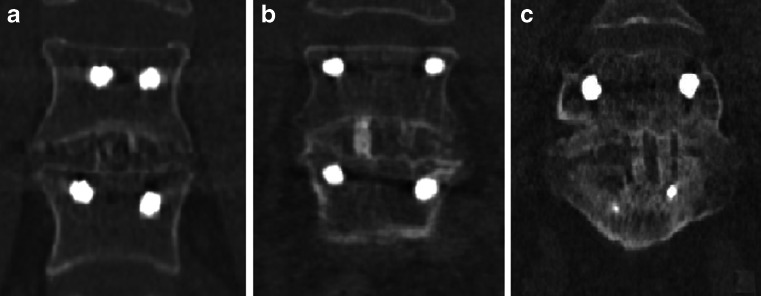

Fig. 2.

Examples of CT fusion scores 0 (a), 1 (b) and 2 (c)

The 18F-fluoride PET/CT scans were evaluated by two independent blinded observers (M.P., B.B.) who determined a volume of interest (VOI) for 18F-fluoride uptake calculation and scored bony bridging based on the standard diagnostic CT scans. Afterwards, discrepancies between the observers were resolved by consensus. Scoring was verified by an orthopaedic surgeon (P.W.) and a musculoskeletal radiologist (R.W.). Interbody fusion between the upper and lower vertebrae was classified on the diagnostic CT scan as: the presence of a bony bridge (Fig. 1) on both sides either within or around the cages (score 2); the presence of a bony bridge on one side within or around a cage, right or left (score 1); or no bridging (score 0). Examples of these fusion scores are shown in Fig. 2. On each low-dose CT scan, three ellipsoid VOIs were manually drawn following the contours of the vertebrae (slice thickness 4 mm, short axis range 40 – 50 mm, long axis range 55 – 65 mm), including the intervertebral disc space and upper and lower endplates of the segment operated upon (Fig. 3a). These VOIs were then transferred to the coregistered attenuation-corrected PET image (Fig. 3b), and in each of these VOIs, the SUVmax was determined, i.e. activity in the upper, lower endplates and the intervertebral disc space (SUVmaxU, SUVmaxL and SUVmaxD, respectively), as well as the ratios of the upper and lower endplate activities to the intervertebral disc space activity (SUVratioU and SUVratioL, respectively).